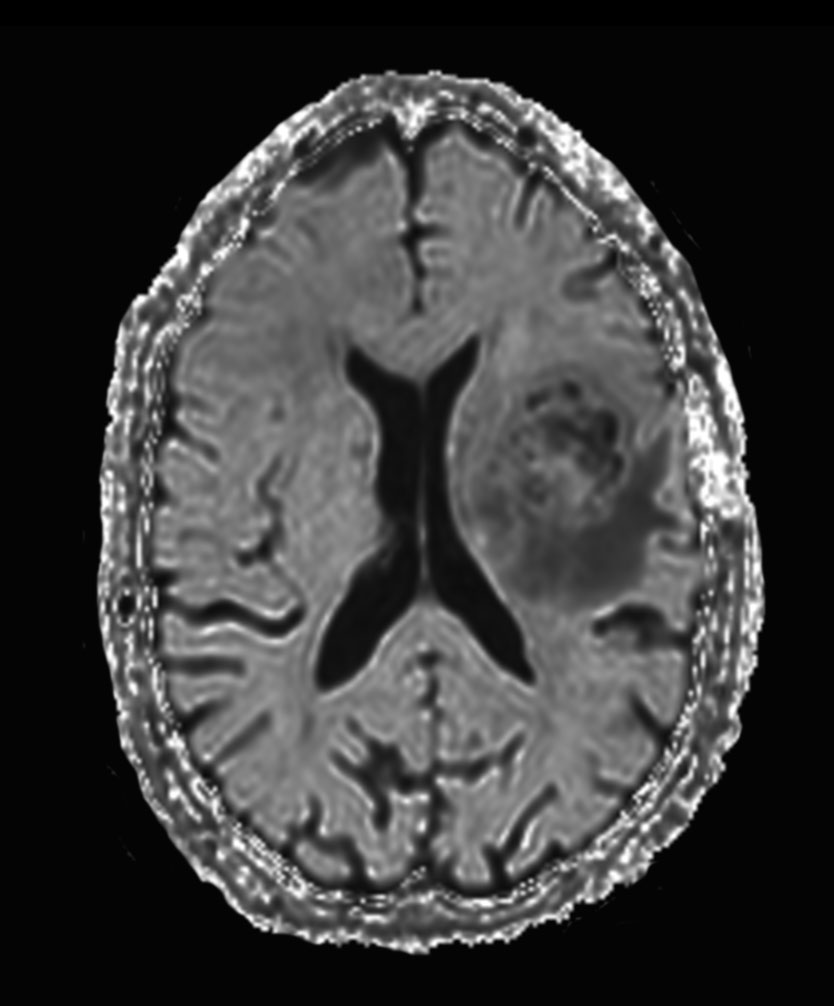

Axial SWIp